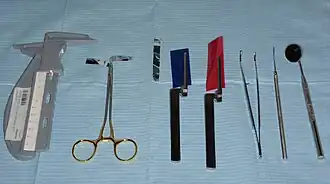

Instruments Required

- Miller’s forceps

- Articulating paper

- Shimstock

- Mosquito forceps

- Mirror

- Dental probe

- Willis gauge